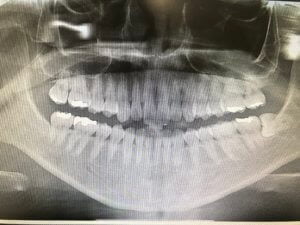

わたしの親知らずは横に生えてるタイプで、頭が半分しか出ていないものでした。

この歯の生え方の場合、歯を分割したり、歯肉を切ったりしなきゃいけない、と授業で習いまして、ビビっていました。

ちなみに、わたしの親知らずは神経に近く、どの歯医者に行っても